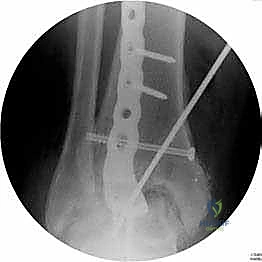

خطوات جراحة تثبيت مفصل الكاحل الأمامي بالتفصيل (Step-by-Step Surgical Procedure)

تُجرى العملية تحت التخدير العام أو النصفي (الشوكي)، وتستغرق عادةً بين ساعتين إلى ثلاث ساعات، وتتطلب دقة ومهارة فائقتين. إليكم الخطوات الجراحية كما ينفذها الأستاذ الدكتور محمد هطيف:

1. الوضعية والشق الجراحي (Positioning and Incision)

يستلقي المريض على ظهره (Supine position). يتم استخدام عاصبة (Tourniquet) حول الفخذ لتقليل النزيف وتوفير رؤية واضحة. يقوم الدكتور هطيف بإجراء شق طولي أمامي فوق مفصل الكاحل، عادة بين وتر العضلة الظنبوبية الأمامية (Tibialis Anterior) ووتر العضلة الباسطة الطويلة لإصبع القدم